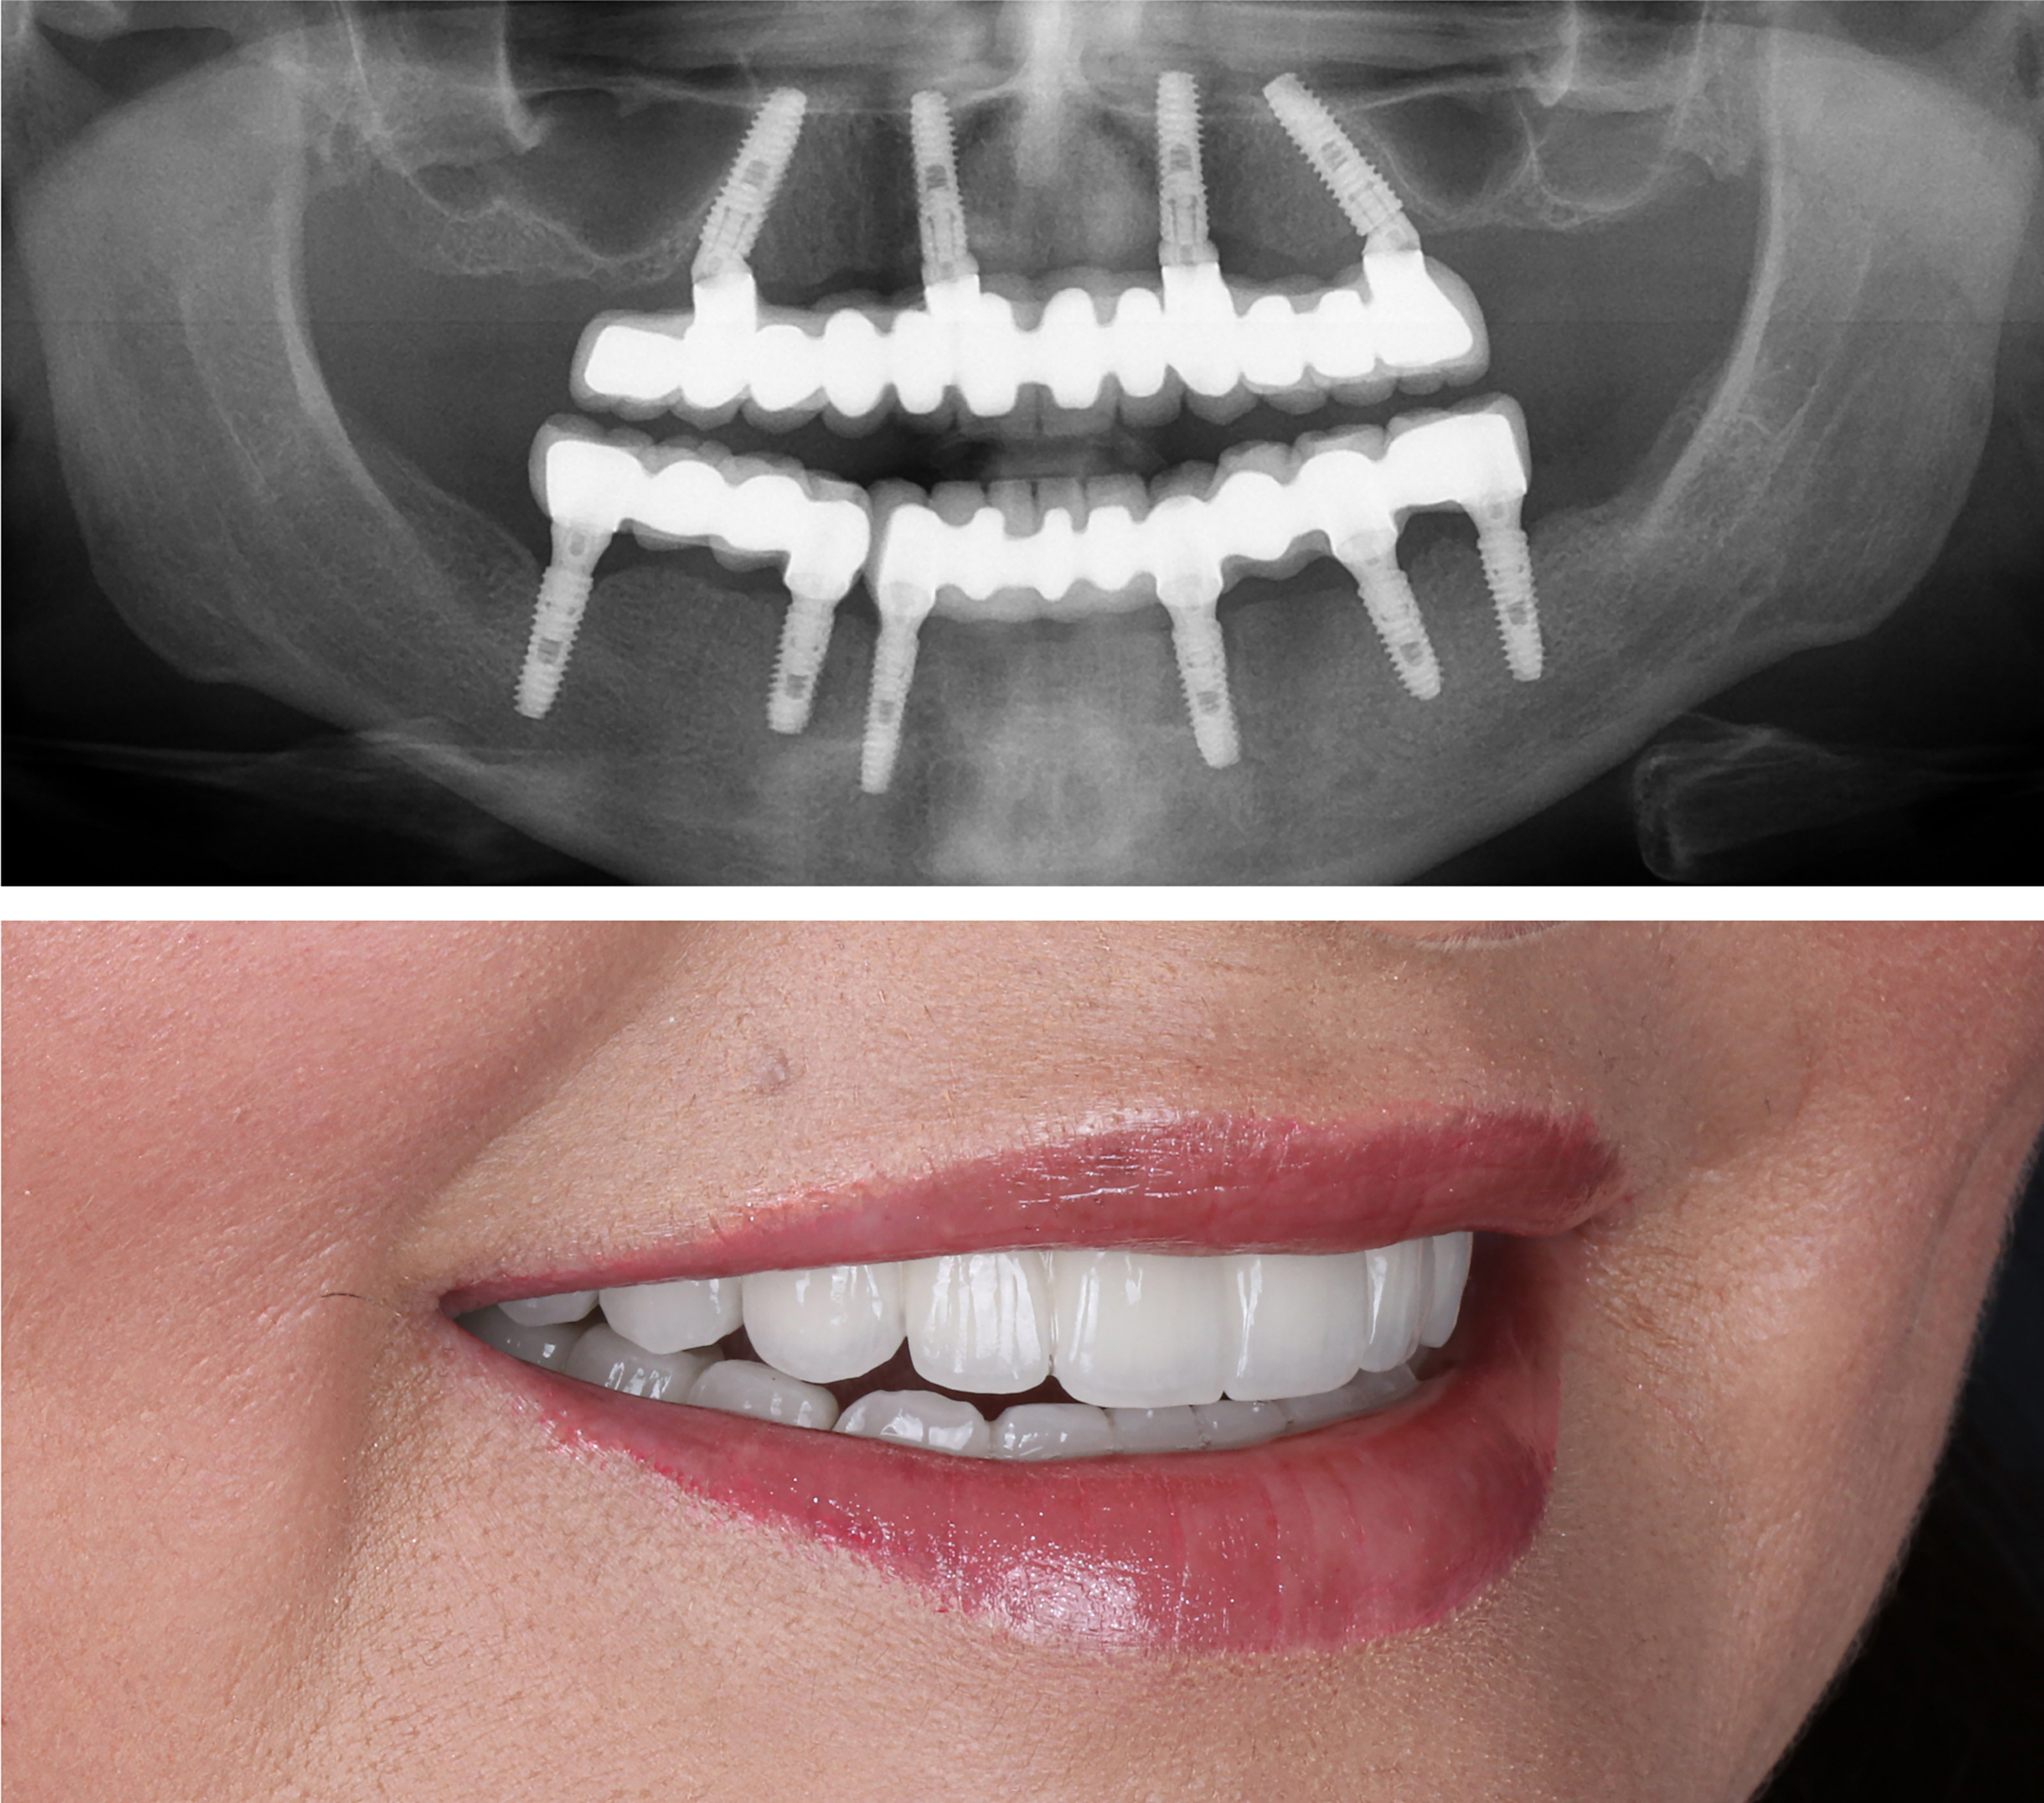

Example transformations achievable with dental implants

Starts as low as $9,999. Can Be Financed $175/mo*

Includes everything from start to finish. No hidden fees.

Includes extraction of all remaining damaged teeth. ($4000 Value)

Includes local sedation for FREE. ($2500 Value)

Includes surgical placement of 4 to 6 implants.

Includes healing teeth.

Includes final ultra aesthetic teeth.